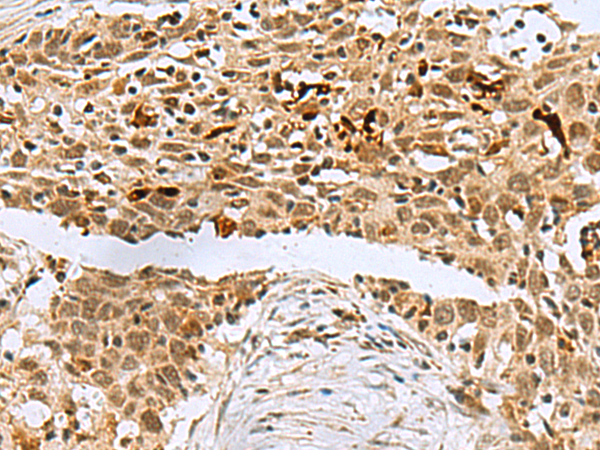

IHC positive control: |

Human ovarian cancer and Human thyroid cancer |

IHC Recommend dilution: |

50-200 |